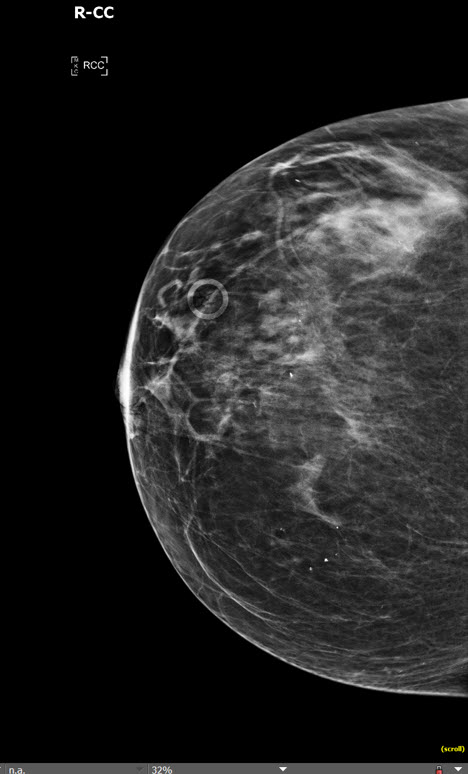

Info Images Findings Impression Reco/Acuity Case Images View Images / Launch Visage Case Notes History Screening mammogram; the 43 yo patient is asymptomatic. Exam Bilateral CC and MLO (2D) + Bilateral CC and MLO Tomosynthesis (3D). Prior Study None or previous exam not available Dicom View Reference Material

Section 1 Submit Findings Case293 Findings Technique The exam is under/over penetrated. Yes No The exam is limited by patient motion. Yes No The exam is limited by exclusion of tissue. Yes No The exam is limited by artifact. Yes No Breast Density There is a fibrofatty glandular pattern. Yes No There is a scattered fibroglandular pattern. Yes No There is a heterogeneously dense fibroglandular pattern. Yes No There is an extremely dense fibroglandular pattern. Yes No Mass There is a mass (masses) present. Yes No The mass is right/left/bilateral. Yes No N/A The mass is new. Yes No N/A The mass is stable. Yes No N/A The mass is low density relative to the breast tissue Yes No N/A The mass is equal density relative to the breast tissue Yes No N/A The mass is high density relative to the breast tissue. Yes No N/A The mass contains fat. Yes No N/A The shape is round, oval, irregular. Yes No N/A There are associated calcifications. Yes No N/A The calcifications are dystrophic. Yes No N/A There are benign intramammary lymph nodes. Yes No Margins The margins of the mass are circumscribed. Yes No N/A The margins of the mass are obscured. Yes No N/A The margins of the mass are indistinct. Yes No N/A The margins of the mass are spiculated. Yes No N/A Calcifications There are calcifications. Yes No The calcifications are right/left/bilateral Yes No N/A The calcifications are new. Yes No N/A The calcifications are stable. Yes No N/A The calcifications are benign (vascular, coarse dystrophic, secretory, skin, milk of calcium). Yes No N/A The calcifications are suspicious (amorphous, coarse heterogeneous, fine pleomorphic, fine linear, fine linear and branching). Yes No N/A The calcifications are diffusely distributed. Yes No N/A The calcifications are regionally distributed. Yes No N/A The calcifications are grouped. Yes No N/A The calcifications are segmentally distributed. Yes No N/A The calcifications are linearly distributed. Yes No N/A Asymmetry There is an asymmetry (focal, regional, global). Yes No The asymmetry is right/left/bilateral. Yes No N/A There is architectural distortion. Yes No The architectural distortion is right/left/bilateral. Yes No N/A Associated Features There is nipple retraction. Yes No The nipple retraction is right/left/bilateral. Yes No N/A There is skin thickening. Yes No The skin thickening is right/left/bilateral. Yes No N/A Axilla There are morphologically abnormal lymph nodes. Yes No The morphologically abnormal lymph nodes are right/left/bilateral. Yes No N/A Subareoalar Region There are abnormal ducts in the subareolar region. Yes No The abnormal ducts in the subareolar region are right/left/bilateral. Yes No N/A Prior Surgery There are implants. Yes No The implants are subglandular/subpectoral. Yes No N/A The implants are saline/silicone. Yes No N/A There are changes related to prior surgery breast reduction/lumpectomy/surgical excision. Yes No The changes related to prior surgery are right/left/bilateral. Yes No N/A